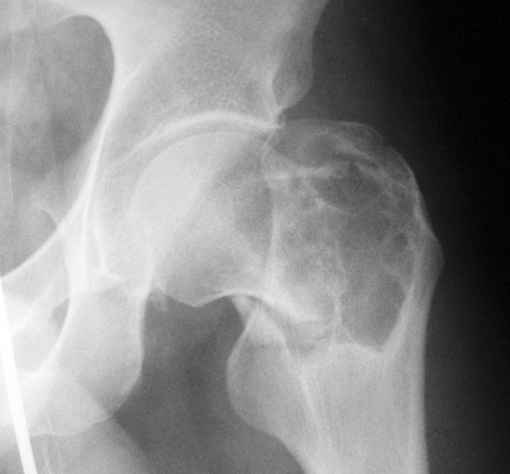

Патологический вертельный перелом

Уважаемые коллеги! Больной (1974 г.р.) травма 26.01.2009г., у пал на ра-боте с высоты своего роста, доставлен в одну из горбольниц Екатеринбурга в травматологическое отделение. На рентгенограмме выявлен патологический перелом чрезвертельной области левого бедра.

Доброкачественная опухоль (ОБК?, энхондрома?), по данным RS. Дополнительно произведено КТ. Наложено скелетное вытяжение.